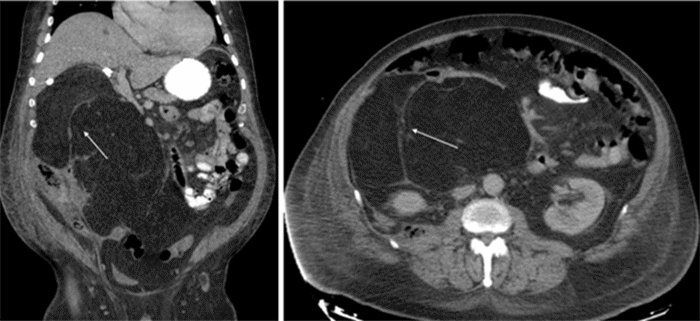

CT imaging at time of presentation to the ED showing multiple ...